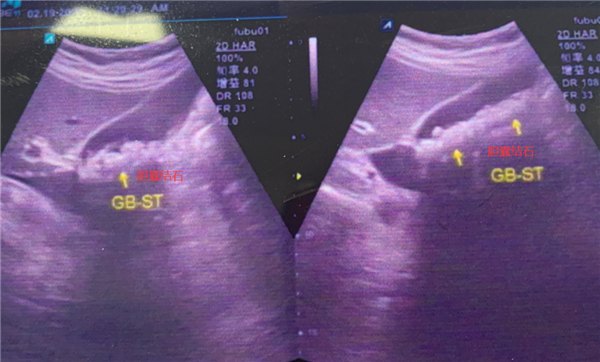

京都醫(yī)院檢查提示,涂婆婆膽囊里有近300顆結(jié)石,最大的有1公分左右。如果繼續(xù)放任不管,結(jié)石將會在涂婆婆膽囊內(nèi)越長越多

并持續(xù)刺激膽囊黏膜,不僅膽囊會被結(jié)石撐大失去功能,甚至還會導(dǎo)致膽囊化膿穿孔,引起嚴(yán)重的急性腹膜炎等。

此外,一旦其膽囊里的小結(jié)石掉到膽總管形成梗阻,還有可能引起梗阻性黃疸、急性胰腺炎、膿毒血癥、感染性休克等問題,危及生命。

為此,醫(yī)院院長、肝膽結(jié)石主任沈章義為涂婆婆制定并實(shí)施了經(jīng)臍無痕保膽取石手術(shù)方案

經(jīng)過一個(gè)多小時(shí)的手術(shù),成功經(jīng)患者肚臍眼位置取出297顆金黃色的小結(jié)石,乍眼看去就像一顆顆“玉米粒”似的,最重要的是,膽囊由于功能完好也被順利保住了!